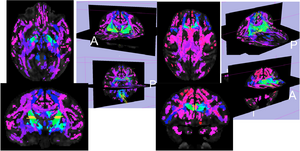

Average cost map computed on the rhesus monkey DWI atlas with the source located in the internal capsule (left) and the genu of the corpus callosum (right). The grayscale overlays show the FA map, and the 3D visualizations include the streamline tractography results from the same seed regions for comparison purposes.